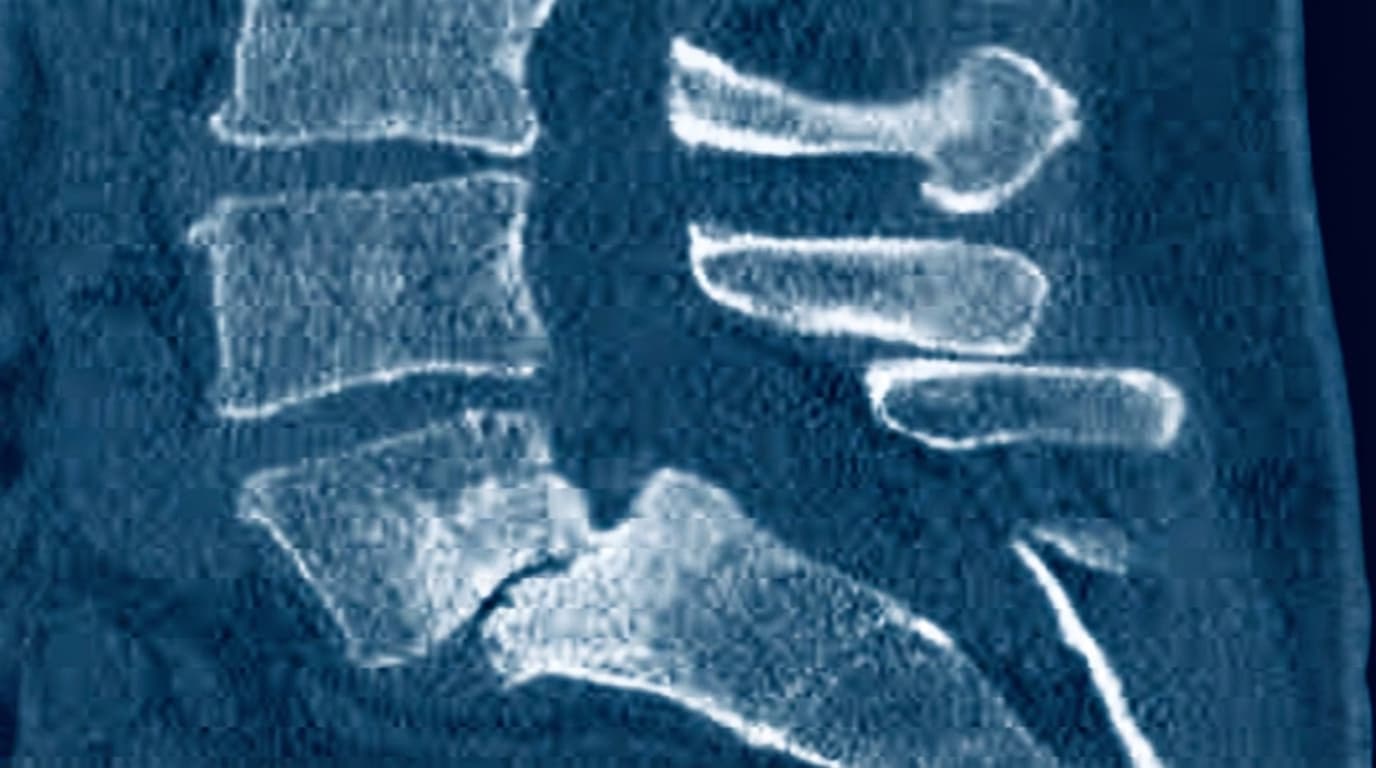

📉 Espondilolistese Ístmica L5–S1

Deslizamento anterior de L5 sobre S1 (sacro) devido a uma fratura prévia no ístmo (espondilólise). Sem a conexão posterior intacta, a vértebra inclina para frente. É mais comum em adolescentes e jovens adultos, especialmente atletas com história de espondilólise.